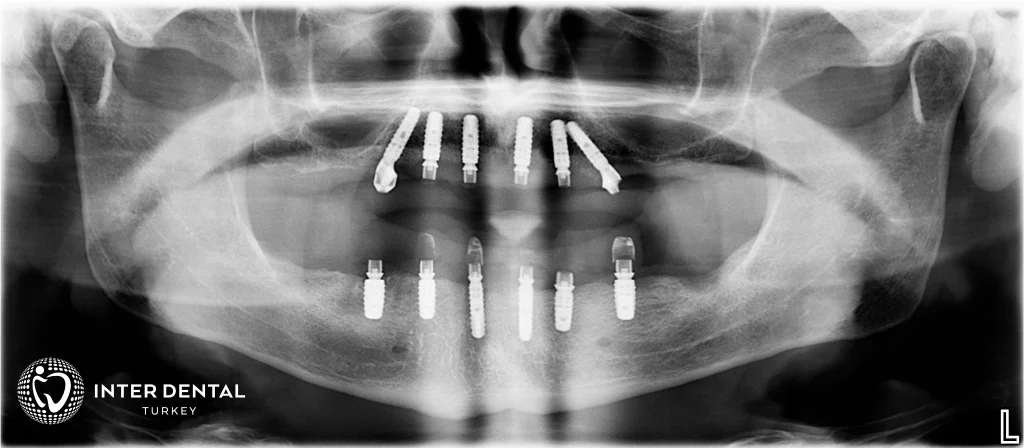

Görselde All-on-Six implant tekniği gösterilmektedir. Çene kemiğine yerleştirilen 6 titanyum implant, üstten vidalanarak sabit protezin desteklenmesini sağlar. Böylece tüm dişlerin eksikliğinde dayanıklı ve doğal görünümlü sabit bir çözüm elde edilir.

All on six implant tekniğinde çene kemiği içerisine titanyum vida yerleştirilir. Titanyum vidalar hemen hemen eşit mesafede olacak şekilde konumlandırılırlar. Böylece çenenin ihtiyaç duyduğu gücü sunarlar. Kuron kısımları ise porselen ya da zirkonyumdan üretilirler.

Rehberli cerrahi ile her arça altı titanyum implant yerleştirilmesi

All on six implant tedavilerinde, all on four implant tedavilerine kıyasla implant sayısı daha fazla olduğu için çene kemiğine iletilen kuvvet dengeli bir şekilde dağılım gösterir. All on four implant ve all on six implant teknikleri tüm dişleri eksik olanhastalara uygulanır.